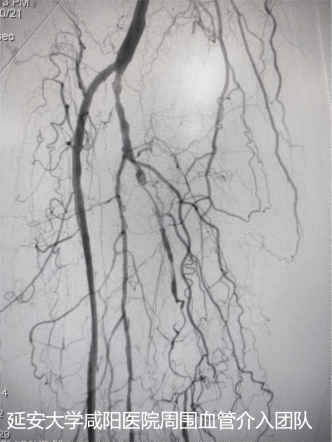

術后DSA

為了保肢,輾轉至我院心血管內科一病區(qū),吳棟梁副院長帶領周圍血管病介入團隊討論、經評估及術前準備后于3月24日對患者進行下肢動脈球囊擴張成形術,術中下肢動脈造影提示膝下脛前、脛后、腓動脈動脈閉塞,血管鈣化嚴重及側支血管形成較差(股腘動脈病變TASC II分型為D型);手術難度較大,手術失敗患者直接面臨截肢,在規(guī)范化的介入操作下最終開通患肢閉塞血管,術后肢體缺血癥狀立即改善,足背動脈搏動恢復;下肢變暖了,疼痛消失了,老爺子及家屬終于舒展開了愁眉,露出了久違的笑容。